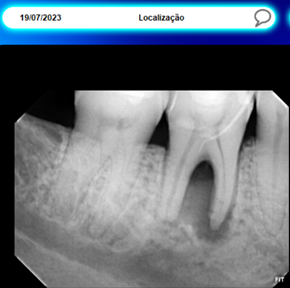

Quase dois anos após sua primeira visita, o paciente retornou à clínica relatando uma alteração notada em uma das lentes de contato dental, especialmente próxima à gengiva. Ao investigarmos, identificamos a presença de uma fístula e realizamos um rastreamento com radiografias (RX). Para nossa surpresa, constatamos a ausência de osso entre as raízes, evidenciando uma drenagem de pus. O paciente, curiosamente, não apresentava dor e o canal não havia sido tratado.

Ao revisarmos o exame inicial de 2021, verificamos que essa lesão não estava presente na primeira consulta. Em um período de quase dois anos, o paciente perdeu um dente devido a fatores como trauma, apertamento dental e a influência da Disfunção Temporomandibular (DTM). Este desfecho é lamentável, destacando que, mesmo para aqueles que mantêm dentes esteticamente atraentes, realizam tratamentos regulares e não aparentam problemas, a DTM pode se manifestar silenciosamente, resultando na perda dentária se a causa subjacente não for devidamente tratada. Este caso sublinha a importância de abordagens abrangentes e preventivas na odontologia, especialmente quando ligadas a condições como o estresse e o apertamento dos dentes.